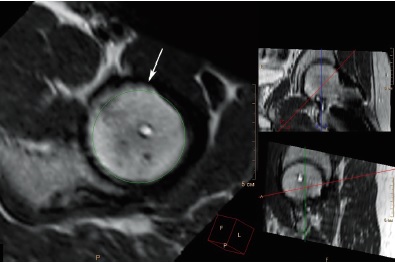

При анализе МРТ, выполненной на 19-м году жизни, установлено, что вышеописанная деформация перехода «головка – шейка» различной выраженности присутствовала в 25 (78,1%) из 32 суставов со смещением эпифиза, величина передневерхнего угла α при этом варьировала в диапазоне от 46° до 71°, в среднем 60,6±7,7° (рис. 3, 4).

Рис. 4. МРТ левого тазобедренного сустава пациента 18 лет 7 мес. через 5 лет 2 мес. после операции, радиальный срез на уровне перехода «головка – шейка», перпендикулярный оси шейки бедренной кости, Т2-взвешенное изображение). Деформация перехода «головка – шейка» (обозначена стрелкой) — избыток костной массы в передневерхней части перехода, нарушающий сферичность головки бедренной кости